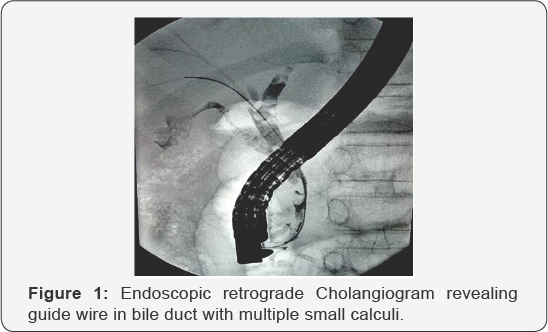

An11-year boy, presented with recurrent episodes of pain abdomen for two months. Evaluation revealed elevated serum transaminases level (ALT-118, AST-230 IU/L, upper limit of normal -40) and alkaline phosphatase level (580 IU/L). Ultrasound abdomen revealed multiple calculi in gall bladder and dilated common bile duct (CBD). Magnetic resonance cholangiopancreatogram confirmed the presence of few small calculi in CBD along with gall bladder stones. Endoscopic retrograde cholangiography was performed under deep sedation in left lateral position. Cholangiogram revealed multiple small calculi in bile duct (Figure 1). Endoscopic biliary sphincterotomy was done and balloon sweep attempted to clear CBD. However, the guide wire could not be retained in position and was inadvertently displaced out. Biliary cannulation was reattempted. Significant resistance was encountered during the passage of guide wire into CBD. On injection of small volume contrast, the CBD could not be opacified. Unexpectedly, portal vein ramifications were visualized on fluoroscopy (Figure 2). The guide wire was immediately withdrawn and biliary cannulation achieved after readjusting the position of sphincterotome guide wire complex. A double pigtail stent (7Fr, 7cm) was placed temporarily. There was no bleeding or any other untoward consequences as a result of inadvertent portal vein cannulation.